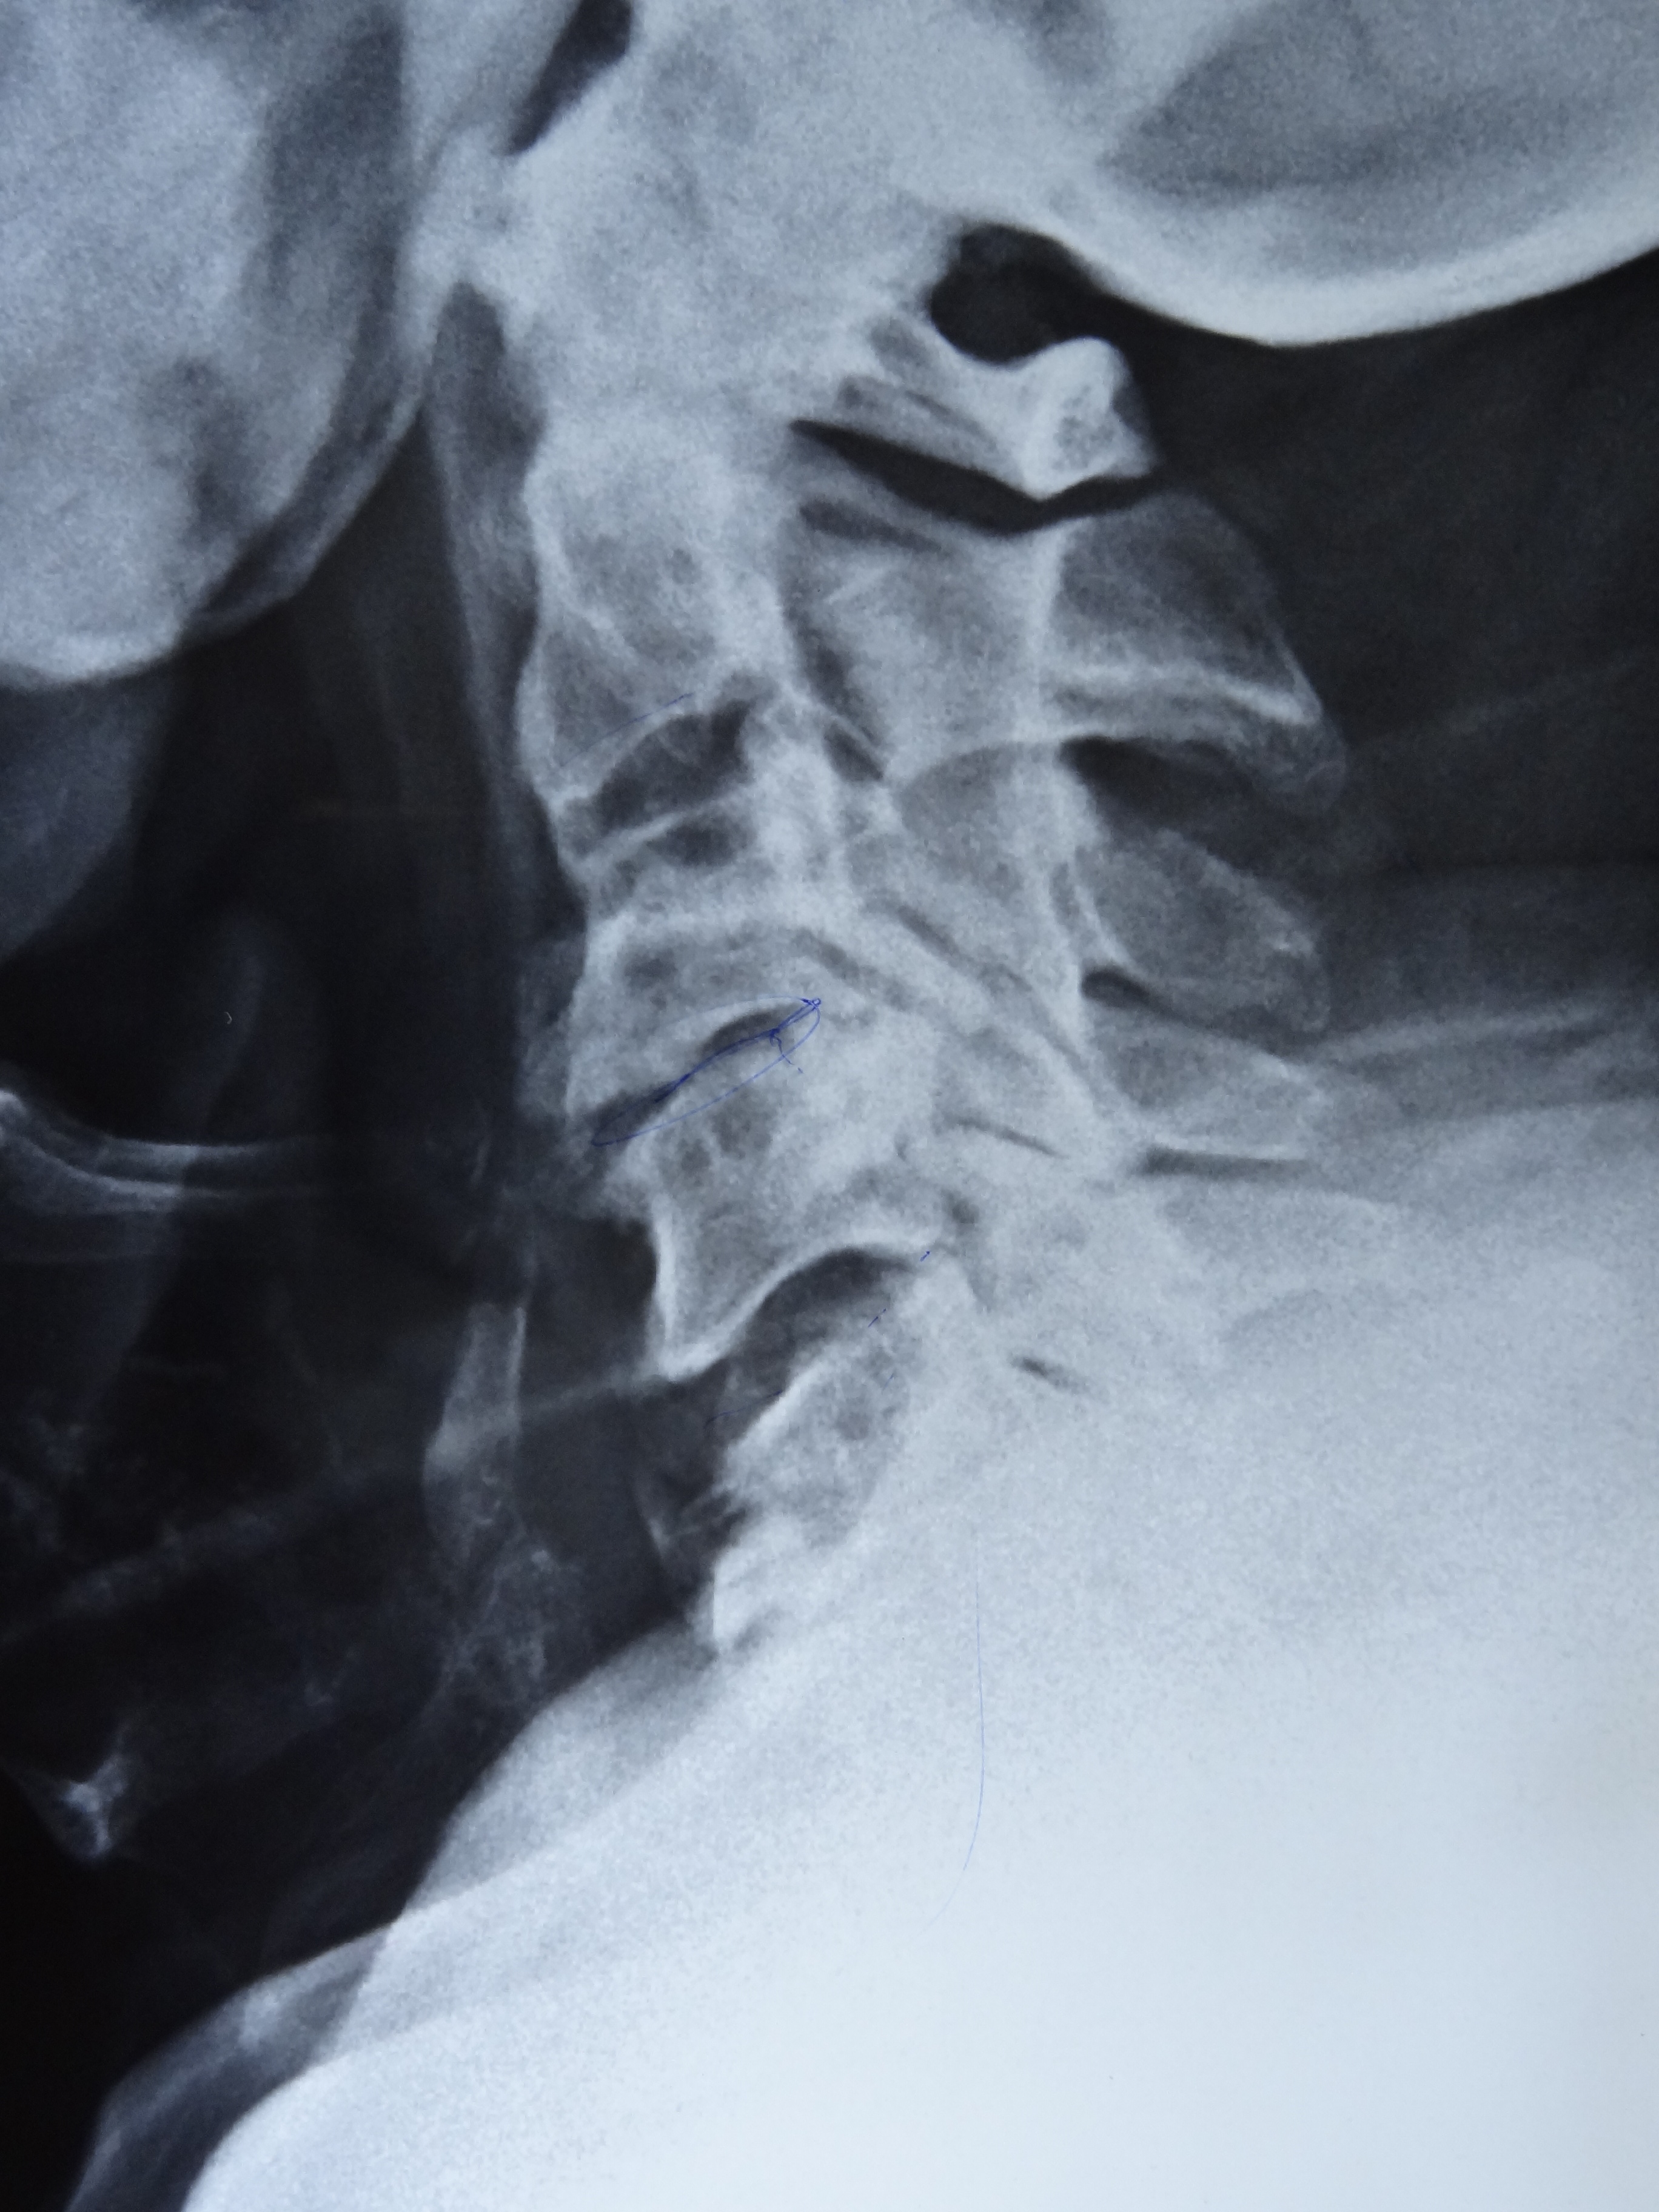

A 70-year-old diabetic and hypertensive male patient visited our clinic with complaints of non-inflammatory back pain since two years. He was heavy built with a BMI of 29 kg/m2. Physical examination revealed limitation of flexion, extension, and lateral flexion of lumbar spine. X-ray of spine revealed flowing calcification of anterior longitudinal ligaments from cervical to lumbar spine with claw osteophytes giving rise to characteristic ‘Melting Wax’ appearance (Panel A: fig A- cervical anteroposterior (AP), fig B- cervical lateral , fig C- lumbar AP , fig D- lumbar lateral) (Panel B: fig E- thoracolumbar AP, fig F- thoracolumbar lateral). Sacroiliac joints were normal (Panel A: fig C- white arrow). The diagnosis was diffuse idiopathic skeletal hyperostosis (DISH or Forestier’s disease) and symptomatic treatment was initiated.